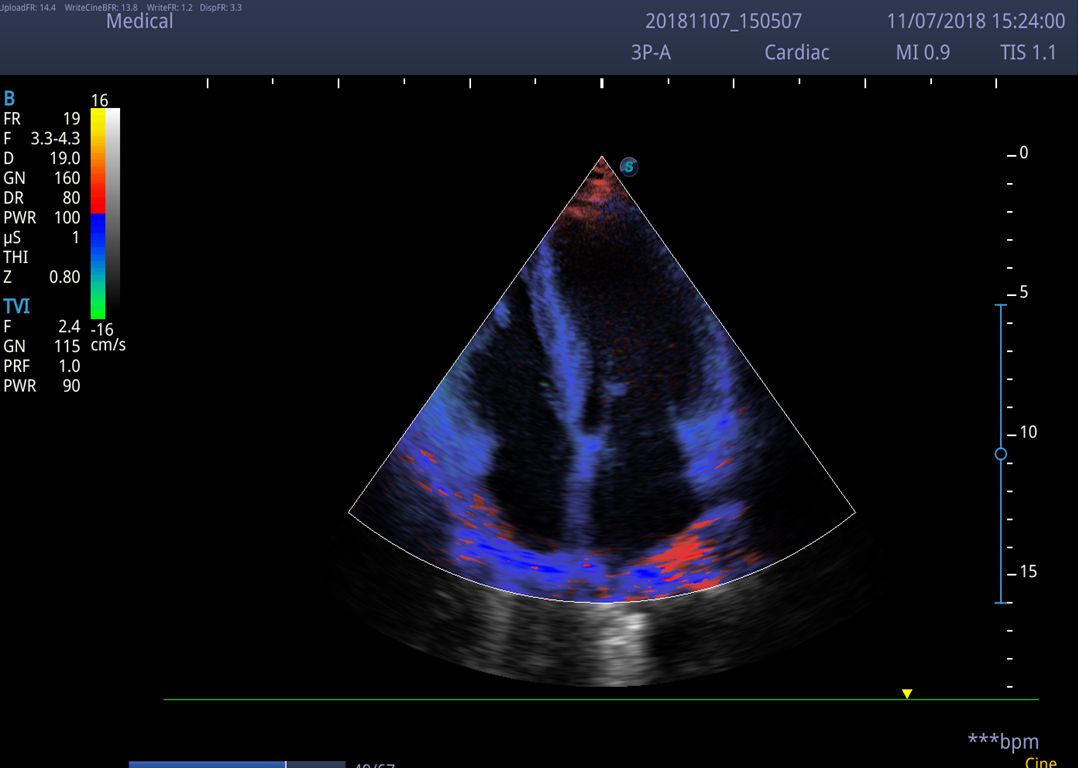

- Chế độ Doppler màu (CFM, PDI/DPDI): giúp đánh giá lưu lượng máu qua tim và mạch máu.

- TDI (Tissue Doppler Imaging): hỗ trợ đánh giá chức năng cơ tim.

Máy siêu âm SonoScape P9 là thiết bị hiện đại ứng dụng rộng rãi trong lĩnh vực y tế, đặc biệt nổi bật trong chẩn đoán tim mạch. Với công nghệ quét 2D tiên tiến, máy cung cấp hình ảnh sắc nét, giúp bác sĩ quan sát chi tiết cấu trúc tim như van tim, cơ tim và nhĩ tim. Ngoài ra, máy còn tích hợp các chế độ Doppler màu, Doppler mạch máu, hình ảnh thời gian thực và tính năng giảm nhiễu, hỗ trợ phát hiện bệnh lý tim mạch một cách nhanh chóng và chính xác.

✔ Chẩn đoán bệnh lý tim mạch: Siêu âm tim qua thành ngực, đánh giá hẹp động mạch, hở van tim, đo vận tốc dòng máu.

✔ Đánh giá chức năng tim: Sử dụng Doppler mô TDI, TDI + PW để phân tích chính xác hoạt động cơ tim.

Chất lượng hình ảnh 2D trên máy siêu âm chuyên tim SonoScape P9: